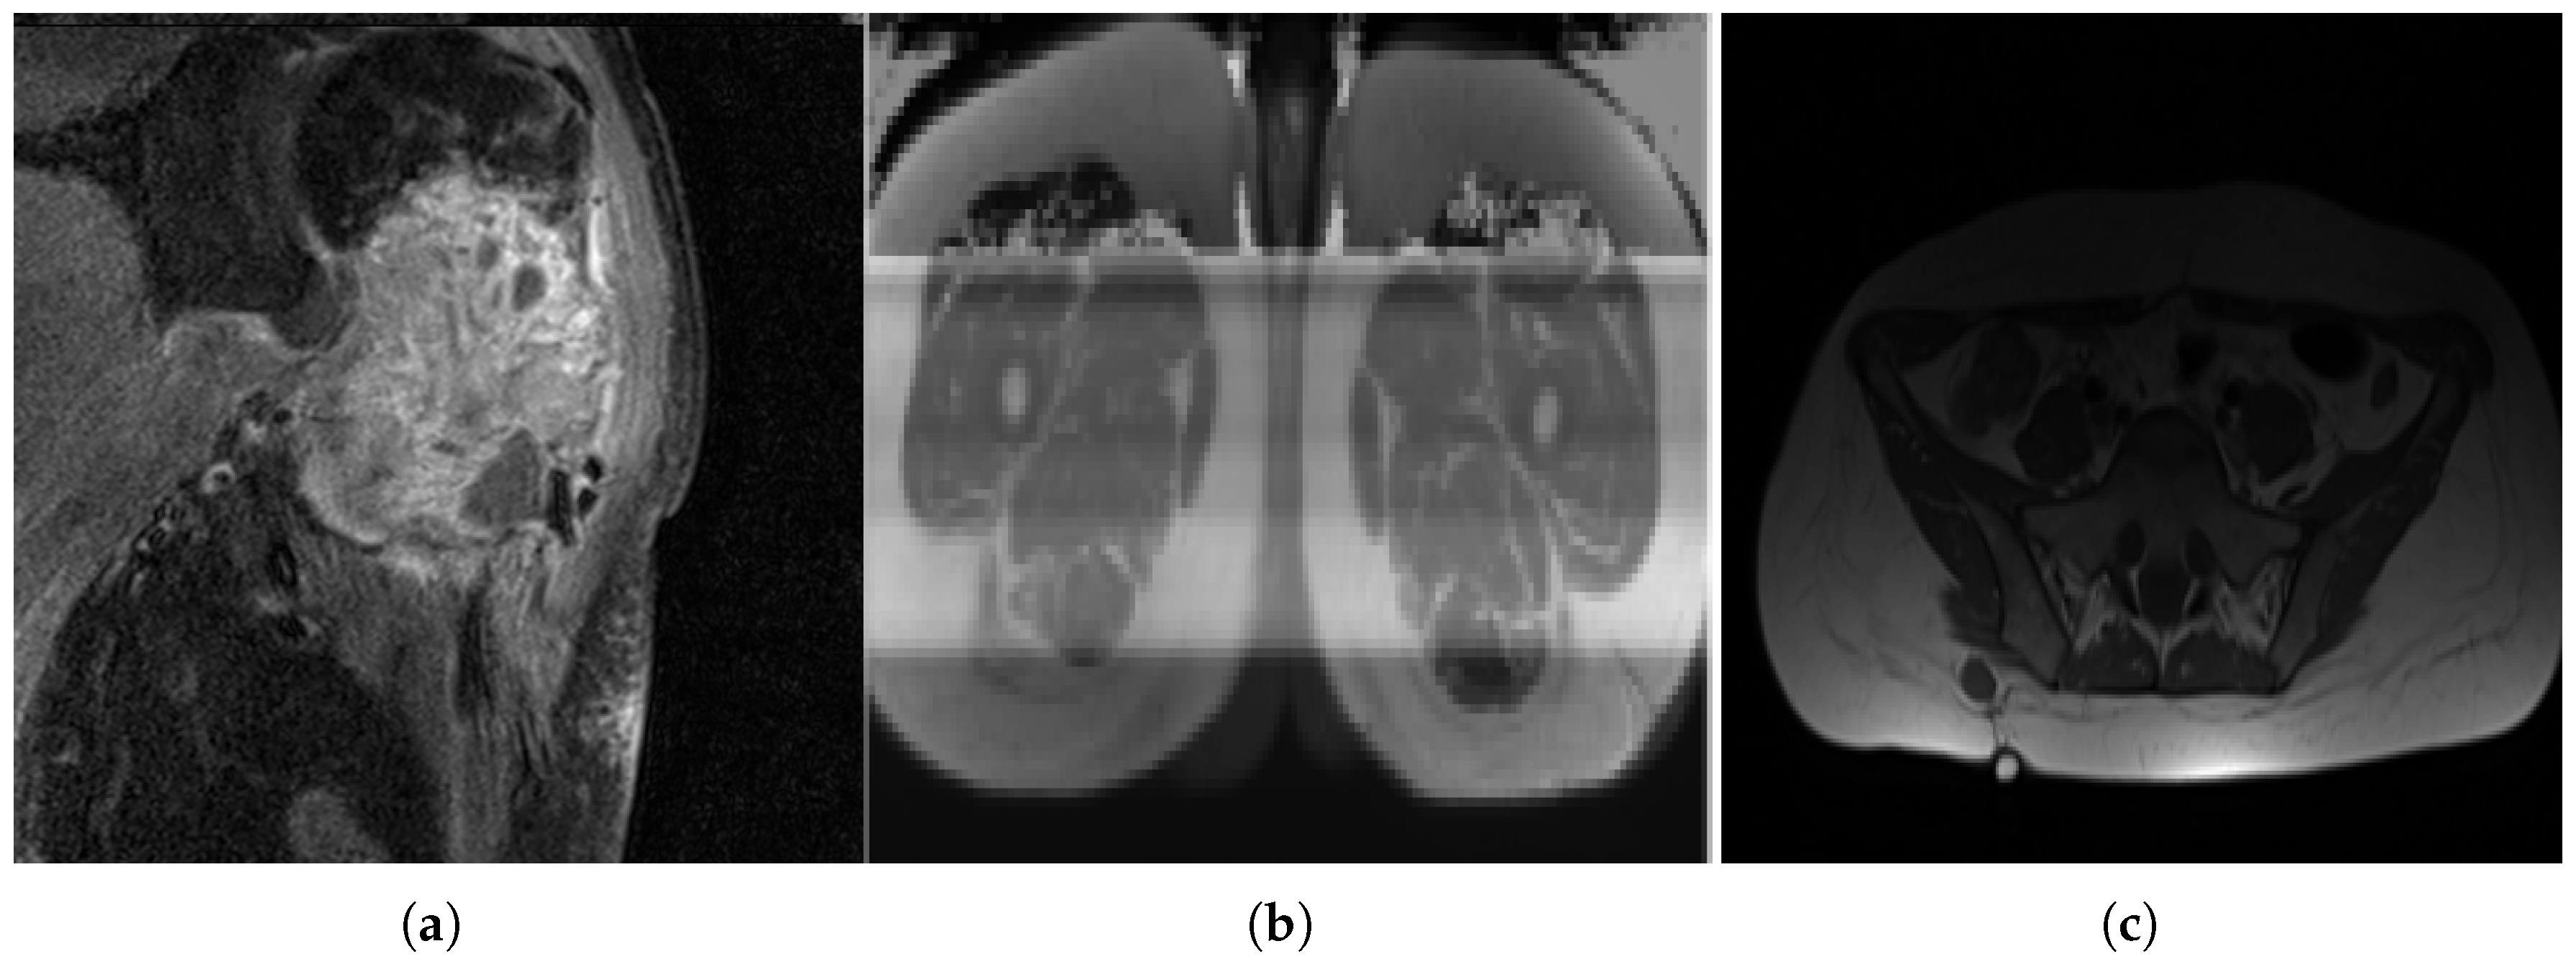

The dataset is complex, as sarcomas are diverse, making generalization difficult [8]. Variations in MRI scan protocols, such as differing contrast, fat suppression and weighting methods, contribute to variability in tumor appearance (Figure 3). Considering multiple orientations—axial, coronal and sagittal—adds complexity that the model must handle. Additionally, differences in gray-value ranges and MRI specifications complicate standardization. Some sarcoma types, like OS, are under-represented, making grade classification challenging, as the model may misclassify OS as a lower grade. Including sarcoma subtype information could improve classification.

Non-pathological tissue was grouped as healthy, which can cause misclassification, as biological tissue may resemble pathological regions (Figure 4). Small homogeneous regions in segmented 3D images may confuse the model, especially when similar to healthy tissue. Image quality varied significantly between patients (Figure 5), with some images being grainy, blurred or corrupted, which may affect model performance.

Figure 3. MRI slices: (a) A case of OS where the machine uses specific settings and contrast media to brighten the tumor region and suppress fat response. (b) Another patient (with liposarcoma in this case) where the tumor region is dark in contrast and fat tissue is not suppressed.